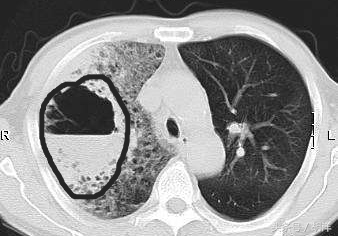

黑圈画出来的是肺烂出来的空洞,上半部分是气,下半部分是脓液